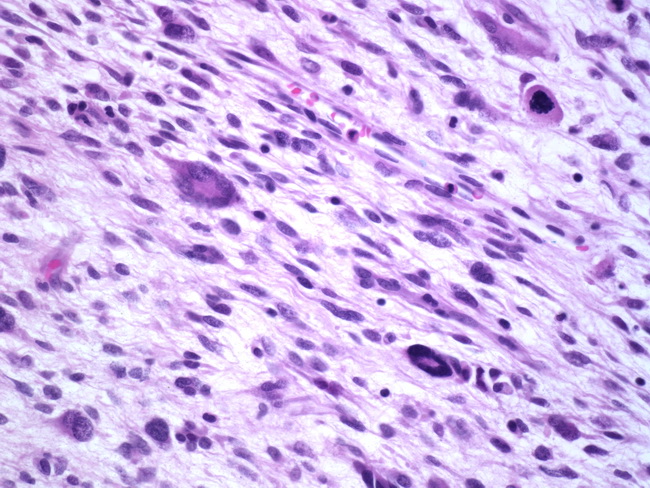

leiomyoma uterus myxoid webpathology comments pathology

leiomyoma myxoid change pathology webpathology comments

uterus myxoid leiomyoma muscle smooth webpathology pathology fibrillary cells nuclei comments